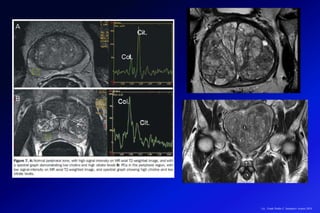

Cuantificar mediante curvas espectrales la existencia de ciertas sustancias en el

cerebro, para facilitar el diagnóstico diferencial de varias lesiones, analizando el

volumen del tejido que contiene la lesión que tenemos que estudiar.

La RM con ESPECTROSCOPIA es una técnica imageneológica no invasiva que

permite la investigación de patologías metabólicas del cerebro.

Esta última nos da información

acerca de metabolitos cerebrales

biológicamente relevantes,

incluyendo el lactato, el N-acetil

aspartato, la creatina total, la

glutamato/glutamina y la colina.

El desarrollo de la técnica de la resonancia magnética (RM), incorporando

la valoración anatómica de alta resolución de la próstata conjuntamente con

la información metabólica (RM espectroscopía), proporcionan hoy en día el

método de imagen de elección para estadiaje del cáncer de próstata.

La RM ofrece la posibilidad de

evaluar no solamente la anatomía

prostática, sino que además es

posible obtener información

metabólica de la glándula mediante

curvas de espectroscopía con una

secuencia específica y ofrece la

valoración más fiable en el estadiaje

local y regional